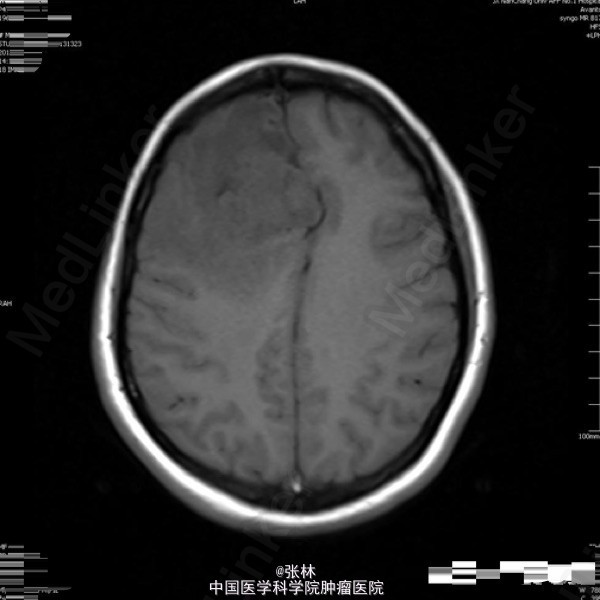

42岁女性,10余天前无明显诱因出现头痛,并呕吐胃内容物,双眼视物模糊。影像学表现:右侧额叶见一不规则形占位性病变,大小约为3.7×4.0×4.5cm,T1WI呈等、低信号,T2WI呈等、高信号,DWI仍呈高信号,周围脑组织少量水肿,增强扫描后病变呈明显强化,边缘水肿无强化。 病理: 镜检:肿瘤细胞弥漫增生,呈乳头状、腺样,细胞核卵圆形,深染。 免疫组化示:GFAP(散在细胞+)、Vimetin(+)、S100(-)、CK(+)、EMA(+)、ki-67(5%+)、CD99(部分+)、CD56(+)、NF(-)、CD34(-)、Hepa(-)、AFP(-)、mammaglobin(-)、RCC(-)、WT-1(-)、CD10(-)、CK7(-)、CK20(-)、Villin(-)、CR(-)、MC(-)、MOC31(-)。及少许脂肪组织,上皮混合组成。 讨论: 室管膜瘤来源于脑室与脊髓中央管的室管膜细胞或脑内白质室管膜细胞巢的中枢神经系统肿瘤。在胶质瘤中占6%,男多于女,多见于儿童及青年,约75%位于幕下,幕上仅占25%。文献报道幕上室管膜瘤75 ~85 %位于脑室外。脑实质内室管膜瘤起源于室管膜细胞嵴,可能是神经管内折叠时形成畸形的结果,好发部位为丘脑,其次为额叶、颞叶、顶叶。实性多见于成人,囊性多见于青少年。 幕上室管膜瘤以头痛、呕吐、嗜睡、厌食及复视等颅高压症状为主,多有局部运动功能障碍和癫痫。